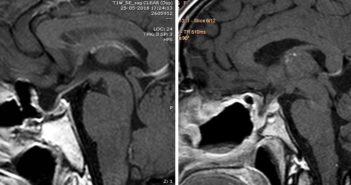

Estos adenomas producen síntomas que provienen de la hormona segregada en exceso, los que pueden ser muy diferentes entre casos y su identificación suele ser compleja.

En la comunidad internacional, esta operación es un procedimiento estándar para los tumores de hipófisis…